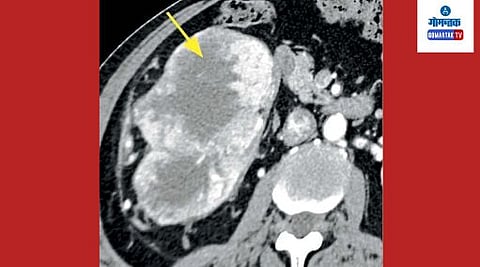

२५ सें.मी.x १५ सें.मी. x १० सें.मी एवढा ट्यूमर काढण्यात वरील हॉस्पिटलच्या डॉक्टरांनी यश प्राप्त केले आहे. त्याआधी या रुग्णाच्या सर्व तपासण्या (ट्रीपल फेज सीटी, सीटी चेस्ट, ह्रदयविषयक चाचण्या, फुफ्फुसविषयक चाचण्या) पूर्ण झाल्यानंतर त्यांच्यावर राईट रॅडिकल नेफ्रॅक्टॉमी शस्त्रक्रिया करण्यात आली.